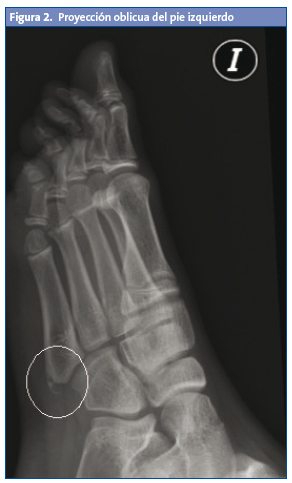

Posteriormente, es valorado por su pediatra, que observa tumefacción no dolorosa también en el pie izquierdo; al tratarse de un preadolescente que realiza deporte de forma habitual, sin un antecedente traumático conocido, y ante la sospecha de posible apofisitis, decide realizar una radiología bilateral oblicua, que presenta una imagen de fragmentación en la base del quinto metatarsiano de ambos pies (Figs. 2 y 3).

La confirmación diagnóstica nos la proporciona la radiología oblicua4,5, ya que la anteroposterior y la lateral pueden no mostrar con claridad el centro de osificación. En dicha radiografía oblicua, podemos observar un aumento o fragmentación de la epífisis y un ensanchamiento de la unión cartilaginosa. La proyección oblicua y la radiología comparativa de ambos pies son de gran utilidad para la confirmación diagnóstica.